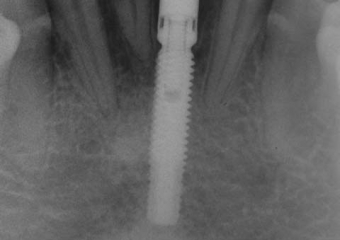

Imagens do elemento 31, apresentando extensa reabsorção radicular externa